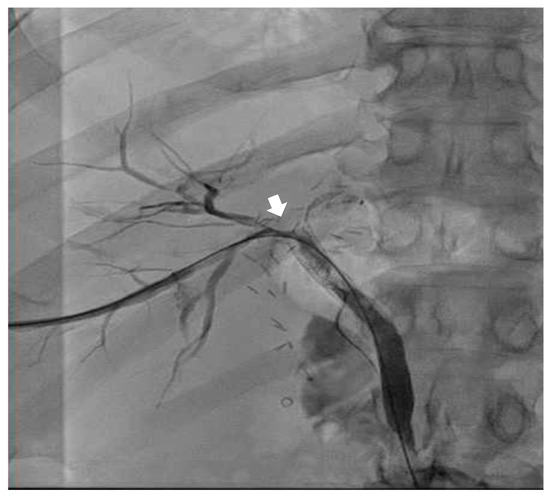

Emergent biliary drain placement with interventional radiology (IR) was performed. The patient remained stable on single-lung ventilation. The IR team noted a biliary pleural fistula (T + 180 min) with connection to the right airway (see Figure 1). During the procedure, more bilious and bloody secretions were suctioned out of the right lung by DLT. Mean arterial pressure was greater than 65 mmHg during the entirety of the procedure. Pressure support of 15 cmH2O provided adequate ventilation with O2 saturation > 99% during the entirety of the procedure with an average tidal volume of 250 mL. At the end of the procedure, the patient was admitted to the medical intensive care unit (MICU) with the DLT on single-lung ventilation with phenylephrine and propofol on the intravenous line. The external biliary drain had significant bloody and bilious drainage to gravity.

Figure 1. AP contrast fluoroscopy demonstrating BBF post-intubation with DLT in the IR suite. The dashed line tracks the fistula between the biliary tree and the right airway. Contrast clearly demonstrates a tract between the biliary tree and the right bronchus through the BBF. RB = right bronchus; BT = biliary tree.